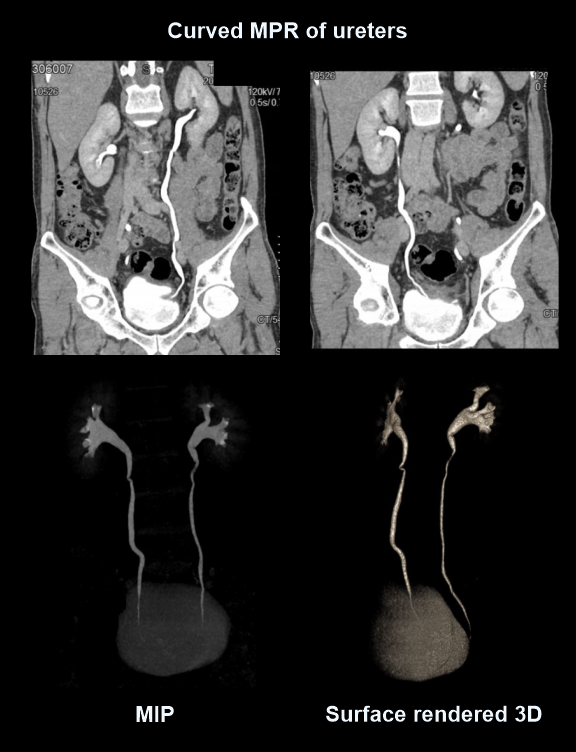

- 3D, MIP, curved MPR images from excretory phase to show ureters.

- Curved MPR images of nephrographic phase to show renal venous system and distance from inferior vena cava (IVC) margin to venous bifurcation.